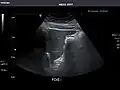

Liver

Ultrasonography of the liver with some standard measurements[6]

In patients with deranged liver function tests, ultrasound may show increased liver size (hepatomegaly), increased reflectiveness (which might, for example, indicate cholestasis), gallbladder or bile duct diseases, or a tumor in the liver.

Ultrasonography of liver tumors involves two stages: detection and characterization. Tumor detection is based on the performance of the method and should include morphometric information (three axes dimensions, volume) and topographic information (number, location specifying liver segment and lobe/lobes). The specification of these data is important for staging liver tumors and prognosis. Tumor characterization is a complex process based on a sum of criteria leading towards tumor nature definition. Often, other diagnostic procedures, especially interventional ones, are no longer necessary. Tumor characterization using the ultrasound method will be based on the following elements: consistency (solid, liquid, mixed), echogenicity, structure appearance (homogeneous or heterogeneous), delineation from adjacent liver parenchyma (capsular, imprecise), elasticity, posterior acoustic enhancement effect, the relation with neighboring organs or structures (displacement, invasion), vasculature (presence and characteristics on Doppler ultrasonography and contrast-enhanced ultrasound (CEUS).